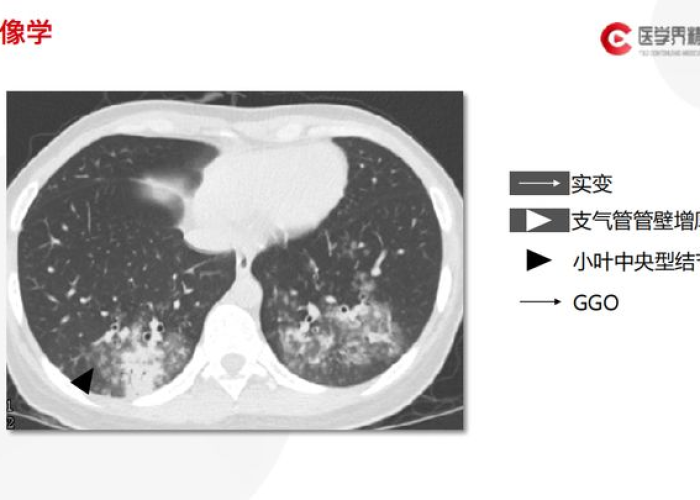

临床数据显示,在肺功能首次出现异常后的6-12个月内是干预的"黄金窗口期",早期确诊并规范治疗的患者,5年生存率可提高30%以上,肺功能下降速度可减缓40%-60%,目前推荐的筛查方法包括:

- 高分辨率CT(HRCT):可发现早期肺间质改变